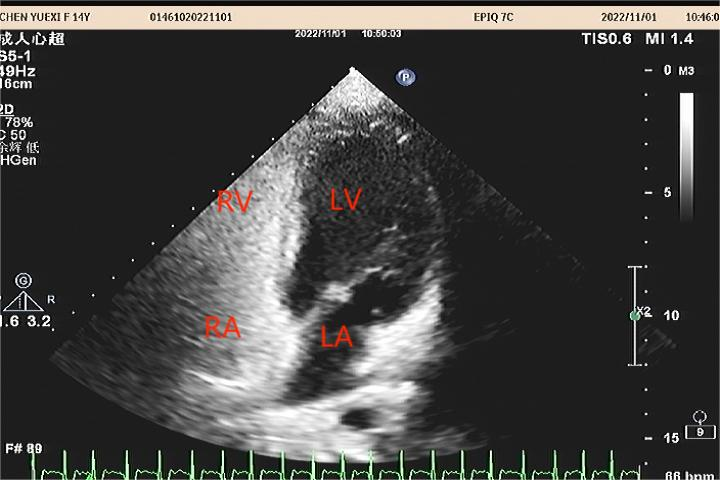

图1:正常情况下左心房压力比右心房压力高3-5mmHg,卵圆孔处于关闭状态,不出现心房间血液分流,如上图所示。